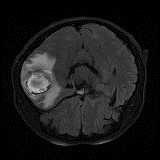

We obtain a subject-wise mean Dice score of 32.94% without any post-processing. By using a simple post-processing with erosion and dilation with filters, this number improves to 48.20% mean Dice score. In comparison, a similar study conducted by [3] consisting of a multitude of algorithms including AnoVAEGAN [4] and f-AnoGANS, obtained a best mean score of 27.8% Dice after post-processing by f-AnoGANS. Before post-processing the best method was Constrained AutoEncoder [8] with a score of 9.7% Dice. An exhaustive list is presented in Table 1. Figure 4 shows sample images of our results.

We obtain a subject-wise mean Dice score of 63.67% for the brain tumor segmentation. Utilizing a simple post-processing scheme of erosion and dilation with filter, we improve our mean Dice score to 68.01%. Figure 4 shows samples generated by our ASC-Net and Table 2 shows our before and after post-processing results. We attempted to apply f-AnoGANs [34] by following their online instructions and failed to generate good reconstructions as shown in Figure 5. The failure of AnoGANs in the reconstruction brings to light the issue with the regeneration based methods and the complexity and stability of GAN-based image reconstruction.